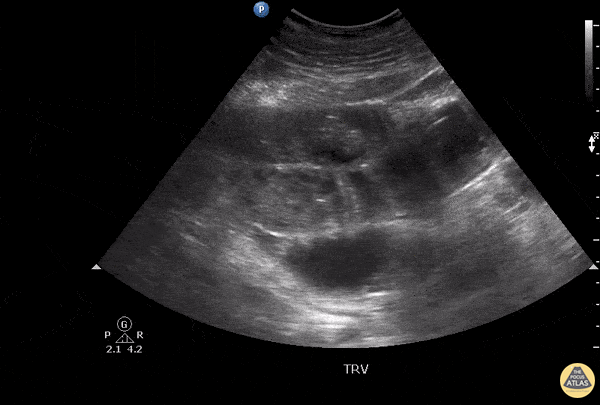

Bowel-GI - Complicated Small Bowel Obstruction

This patient presented with a painful abdomen with distention and absent bowel sounds. Key findings in this scan include ineffective peristalsis as well as colon diameter that exceed 2.5 cm. Anechoic regions suggest presence of fluid which raise concern for a complicated small bowel obstruction. Image courtesy of Robert Jones DO, FACEP @RJonesSonoEM Director, Emergency Ultrasound; MetroHealth Medical Center; Professor, Case Western Reserve Medical School, Cleveland, OH View his original post here